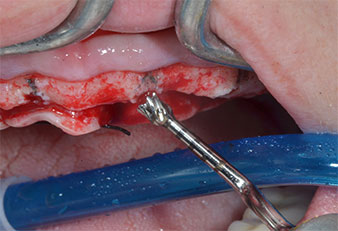

Chirurgisches Instrument Piezomed

Abb. 4: Der nächste Schritt ist die initiale Erweiterung mit den Instrumenten Piezomed I2A/I2P, die in einer horizontalen Drehbewegung verwendet werden.

Ein flammenförmiges, diamantiertes piezochirurgisches Instrument (Piezomed I1) wurde verwendet, um die Implantatpositionen zu markieren und die Pilotpräparationen durchzuführen (Abb. 3). Dabei wurde darauf geachtet, eine Auf- und Abbewegung mit reduzierter Leistung, voller Spülung und niedrigem Druck (unter 300 g) anzuwenden. Als Nächstes wurde ein Pilotinstrument (Piezomed I2A/I2P) zur initialen Erweiterung der Implantatlager auf einen Durchmesser von 2 mm verwendet (Abb. 4), gefolgt von einem 3-mm-Instrument (Abb. 5).